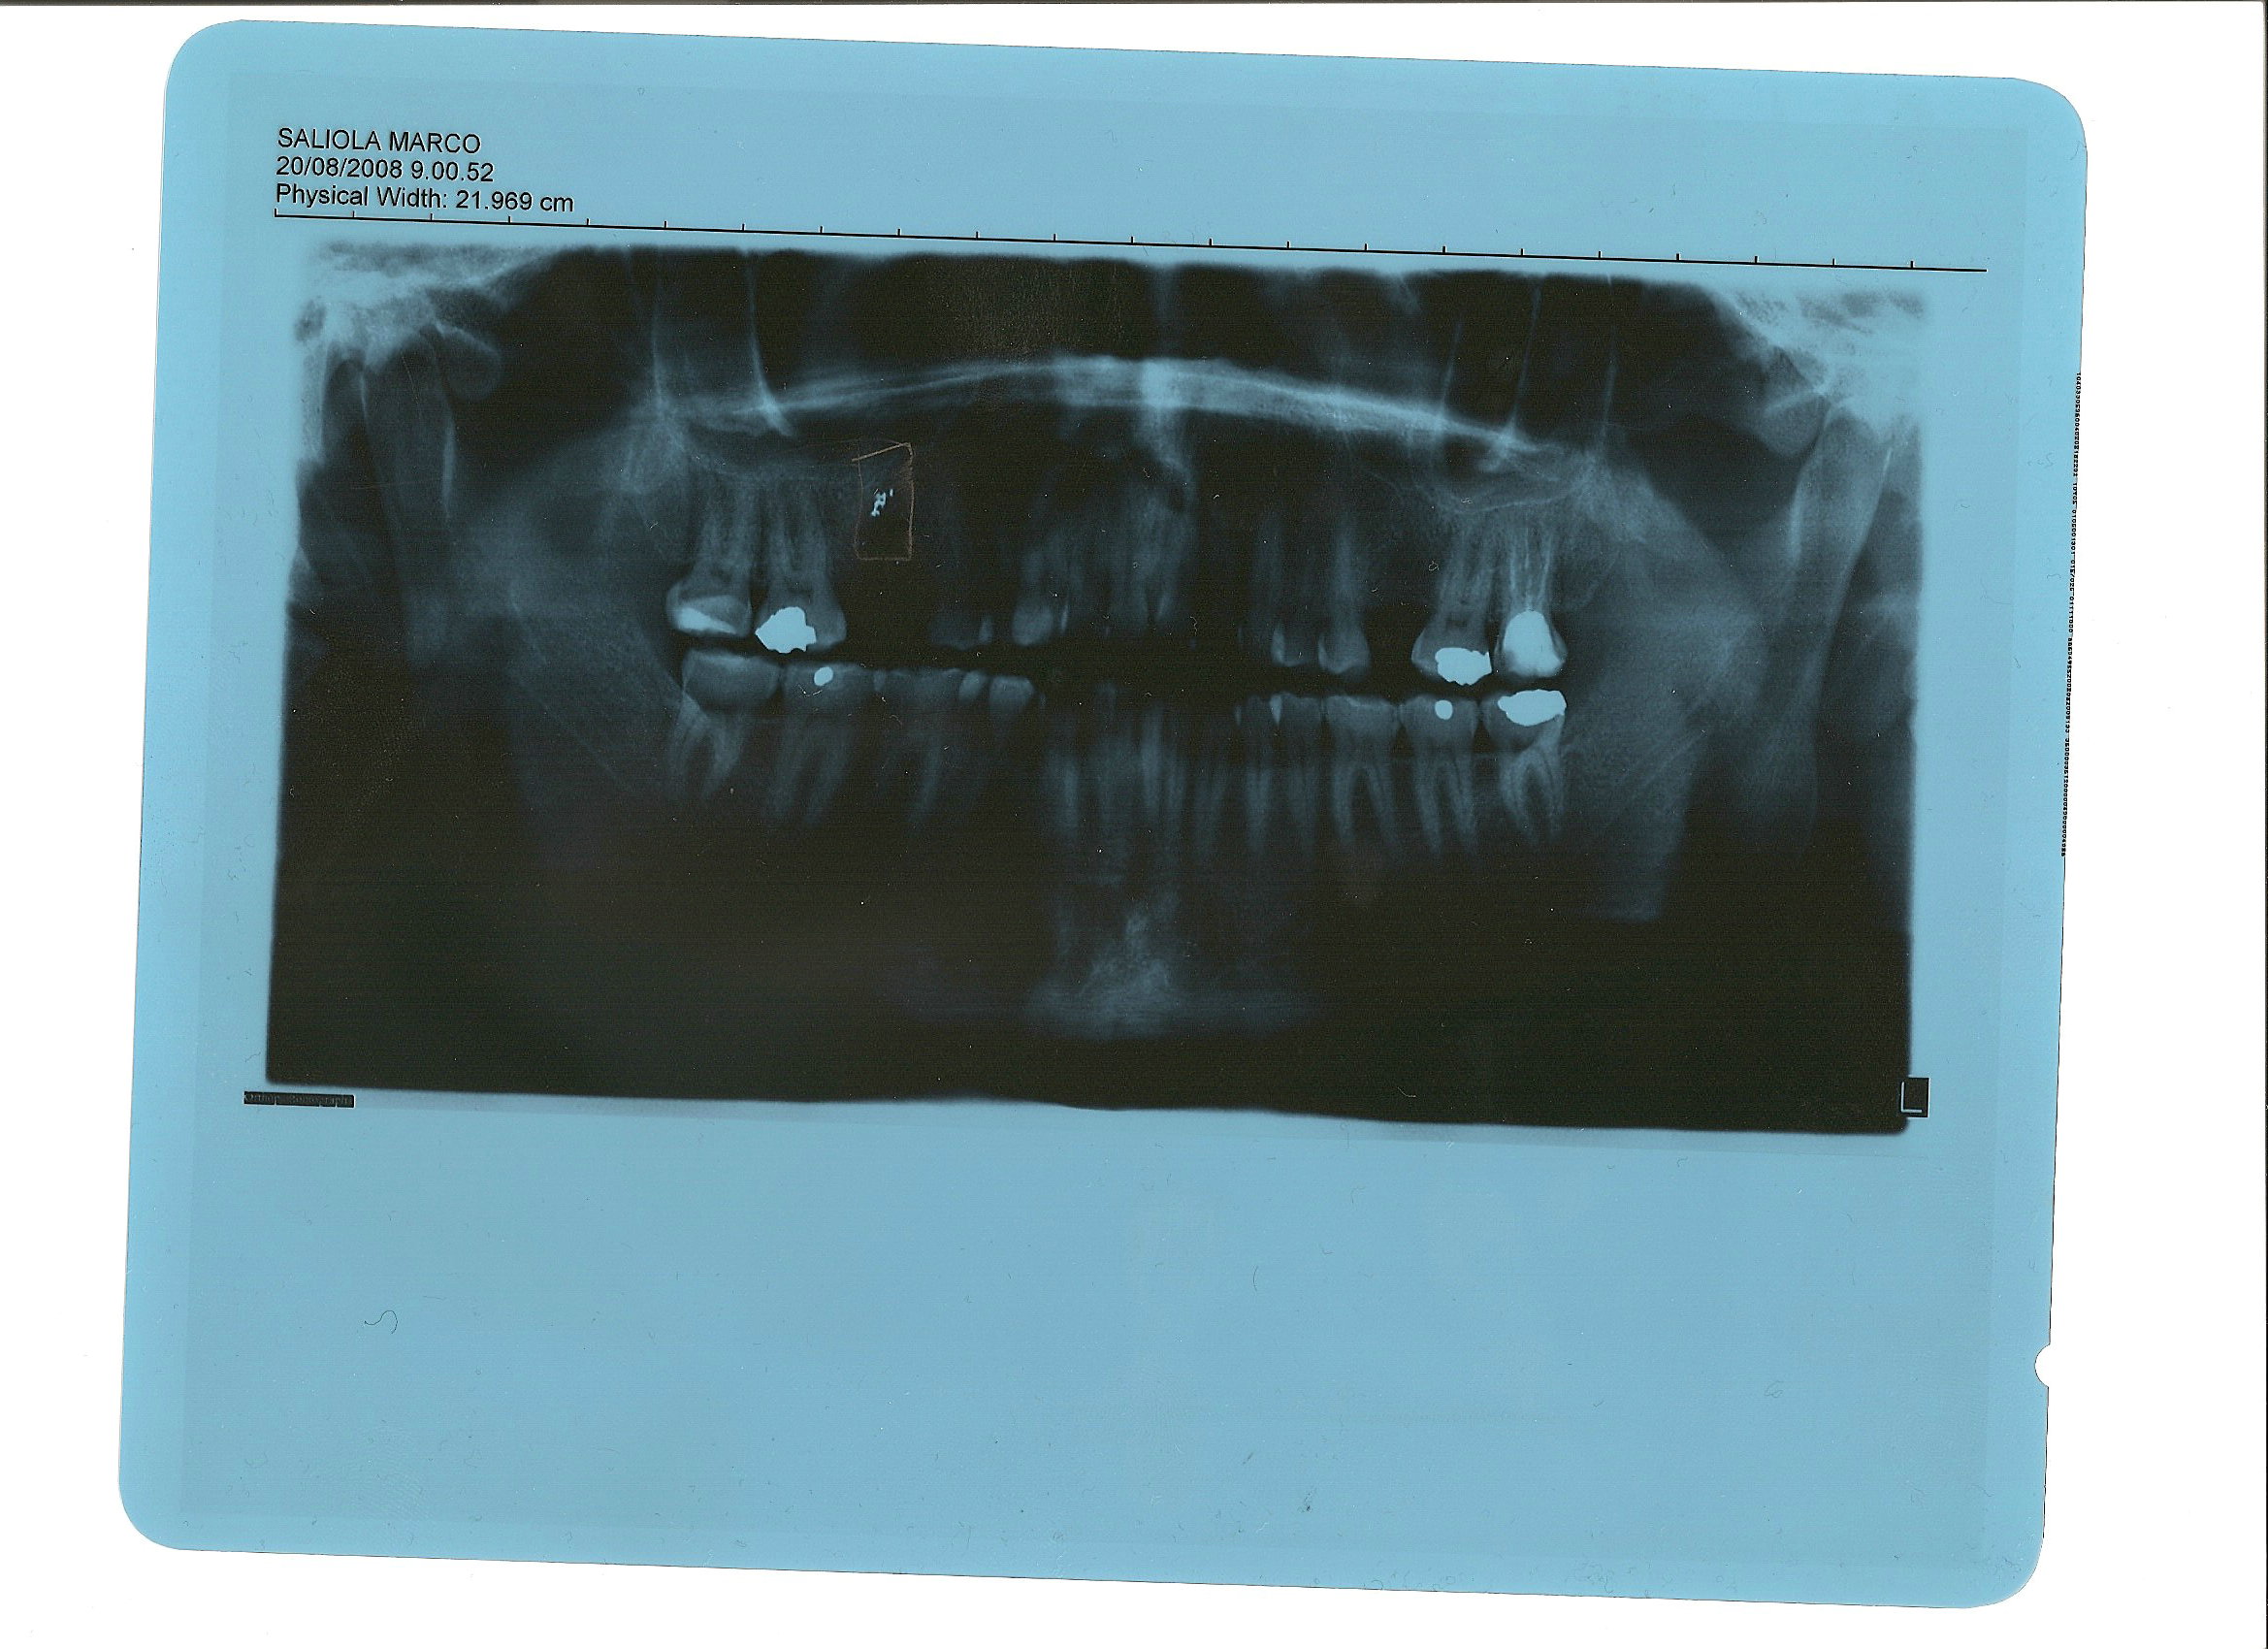

Salve per prima cosa ringrazio tutti quelli che mi hanno risposto e stanno cercando di darmi una mano,anche se è difficile da lontano. comunque vi mando la foto della mia ortopanoramica per farvi vedere quanta amalgama è rimasta nella sede 6+ , valutate voi e spero che cosi vi abbia potuto chiarire meglio le idee di quello che mi